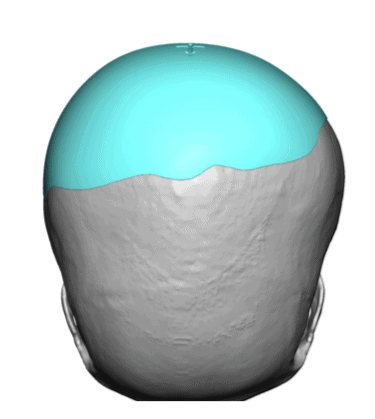

Desire for a higher and more prominent crown of the skull.

Crown of skull augmentation using a custom skull implant.

Desire for a higher and more prominent crown of the skull.

Crown of skull augmentation using a custom skull implant.